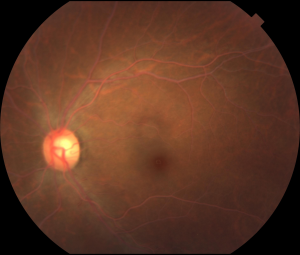

Figures: Right and left eyes of a 43-year-old asymptomatic woman who was referred by an optometrist for abnormal-appearing blood vessels. Visual acuity and examination were normal except for the retinal vessels seen on dilated exam. Note the creamy ‘cake batter’ appearance of the retinal arteries and veins bilaterally. Subsequent serum lab testing revealed an elevated total cholesterol with a triglyceride level >3500 mg/ dl. She was started on oral fenofibrate and niacin which normalized her triglyceride level within 6 weeks. Subsequent dilated exam at that time by the referring optometrist showed a normal fundus appearance (photo unavailable). Photo courtesy of Daniel F. Kiernan, MD, FACS and Barbara McGinley, CRA, COT.

The early signs of lipemia retinalis occur in the peripheral retina, and as triglyceride levels increase, they spread to the posterior pole. At triglyceride levels of 2500–3499 mg/dL, the peripheral vessels appear creamy and thin; at levels of 3500–5000 mg/dL, the vessels in the posterior pole assume a creamy color; and at levels exceeding 5000 mg/dL, the fundus becomes salmon-colored, with creamy arteries and veins that can be distinguished by caliber only. The clinical appearance is graded accordingly as early, moderate, or marked (Stages I-III, respectively).

Signs of lipemia retinalis include peripheral vessels that appear creamy and thin; later in the disease, the vessels in the posterior pole assume a creamy color; and in the most advanced stage, the fundus becomes salmon-colored, with creamy arteries and veins.